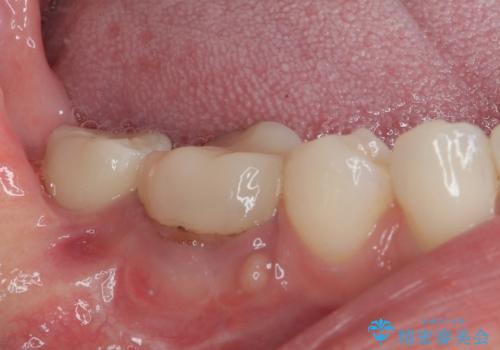

埋伏している右下第二大臼歯は、牽引して咬合に参加させることで計画しましたが、癒着などにより移動困難な場合には、抜歯の上インプラント補綴治療を行うこととしました。

右下の埋伏歯はやはり癒着しており、抜歯の後にインプラントを埋入することとなりました。

埋伏歯の牽引や、奥歯の咬み合わせ改善、インプラント補綴治療と治療期間が延びてしまう要素が多く、治療は難航しましたが、最終的に非常に満足のいく仕上がりとなりました。